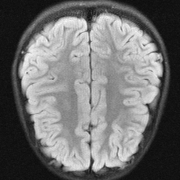

The main consequence of this result is that there is an accuracy-hallucination barrier. If the map ΨΨ\Psi performs too well on a certain image x1subscript𝑥1x_{1} with detail lying close to 𝒩(A)𝒩𝐴\mathcal{N}(A), then it will hallucinate, by incorrectly transferring this detail to another image x2subscript𝑥2x_{2}. Note this situation can arise even when 𝒩(A)={0}𝒩𝐴0\mathcal{N}(A)=\{0\}: if A𝐴A is ill-conditioned then there exist many ‘candidate’ details xDetsubscript𝑥Detx_{\mathrm{Det}} for which AxDet𝐴subscript𝑥DetAx_{\mathrm{Det}} is small while xDetsubscript𝑥Detx_{\mathrm{Det}} is not. In Fig. 2 we demonstrate an example of this effect. A NN is trained to accurately recover a brain image with artificial details. Then when used to reconstruct the detail-free brain image, it hallucinates one of the details. Theorem 4.1 also explains why only one of the details is transferred in this case, and not the other.

xbr+xth+xmisubscript𝑥brsubscript𝑥thsubscript𝑥mix_{\mathrm{br}}+x_{\mathrm{th}}+x_{\mathrm{mi}} xbr+xthsubscript𝑥brsubscript𝑥thx_{\mathrm{br}}+x_{\mathrm{th}} xbrsubscript𝑥brx_{\mathrm{br}}

Refer to caption Refer to caption Refer to caption

Ψ(A(xbr+xth+xmi))Ψ𝐴subscript𝑥brsubscript𝑥thsubscript𝑥mi\Psi(A(x_{\mathrm{br}}+x_{\mathrm{th}}+x_{\mathrm{mi}})) Ψ(A(xbr+xth))Ψ𝐴subscript𝑥brsubscript𝑥th\Psi(A(x_{\mathrm{br}}+x_{\mathrm{th}})) Ψ(Axbr)Ψ𝐴subscript𝑥br\Psi(Ax_{\mathrm{br}})

Refer to caption \begin{overpic}[width=433.62pt]{plots/mod_009_test_im_nbr_004_mod_rec_crop.png} \put(24.0,79.0){\color[rgb]{1,0,0}\definecolor[named]{pgfstrokecolor}{rgb}{1,0,0}\vector(1,-2){6.0}} \end{overpic} \begin{overpic}[width=433.62pt]{plots/mod_009_test_im_nbr_004_rec_crop.png} \put(24.0,79.0){\color[rgb]{1,0,0}\definecolor[named]{pgfstrokecolor}{rgb}{1,0,0}\vector(1,-2){6.0}} \end{overpic}

Figure 2: (Hallucinations due to detail transfer). A trained NN Ψ:mN:Ψsuperscript𝑚superscript𝑁\Psi\colon\mathbb{C}^{m}\rightarrow\mathbb{C}^{N} accurately recovers the detail image in the first column. But it hallucinates by incorrectly transferring the ‘Mickey Mouse’ detail xmisubscript𝑥mix_{\mathrm{mi}} in the first column when recovering the images in the second and third column. The measurement matrix is a subsampled Fourier transform with m/N=20%𝑚𝑁percent20m/N=20\%, which models a MRI acquisition with 555-fold acceleration. See §A for further information on this experiment. Note that the the NN does not transfer the ‘Thumb’ detail xthsubscript𝑥thx_{\mathrm{th}}. Theorems 4.1 and 4.3 shed light on why this is the case.

Fig. 2 presents an example of this result. In this figure, the ‘Mickey Mouse’ detail xmi𝒩(A)subscript𝑥mi𝒩𝐴x_{\mathrm{mi}}\in\mathcal{N}(A), whereas the ‘Thumb’ detail xthsubscript𝑥thx_{\mathrm{th}} has relatively large measurements, i.e., |||Axth|||0\mbox{$|\!|\!|$}Ax_{\mathrm{th}}\mbox{$|\!|\!|$}\gg 0. The NN is trained to recover the image xbr+xth+xmisubscript𝑥brsubscript𝑥thsubscript𝑥mix_{\mathrm{br}}+x_{\mathrm{th}}+x_{\mathrm{mi}}. As a result, it incorrectly transfers the detail xmisubscript𝑥mix_{\mathrm{mi}}, while the detail xthsubscript𝑥thx_{\mathrm{th}} is handled correctly (i.e., it is not transferred). Fig. 4 shows another example of this effect. In this case, A𝐴A is a subsampled Radon transform, which models a CT imaging scenario. Here, the NN is trained to recover the detail image x+xDet𝑥subscript𝑥Detx+x_{\mathrm{Det}}, and as a result, it incorrectly transfer the detail xDetsubscript𝑥Detx_{\mathrm{Det}} when recovering the detail-free image x𝑥x.